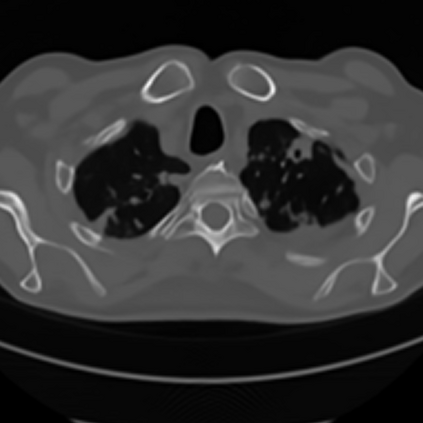

Sparse-view computed tomography (CT) -- using a small number of projections for tomographic reconstruction -- enables much lower radiation dose to patients and accelerated data acquisition. The reconstructed images, however, suffer from strong artifacts, greatly limiting their diagnostic value. Current trends for sparse-view CT turn to the raw data for better information recovery. The resultant dual-domain methods, nonetheless, suffer from secondary artifacts, especially in ultra-sparse view scenarios, and their generalization to other scanners/protocols is greatly limited. A crucial question arises: have the image post-processing methods reached the limit? Our answer is not yet. In this paper, we stick to image post-processing methods due to great flexibility and propose global representation (GloRe) distillation framework for sparse-view CT, termed GloReDi. First, we propose to learn GloRe with Fourier convolution, so each element in GloRe has an image-wide receptive field. Second, unlike methods that only use the full-view images for supervision, we propose to distill GloRe from intermediate-view reconstructed images that are readily available but not explored in previous literature. The success of GloRe distillation is attributed to two key components: representation directional distillation to align the GloRe directions, and band-pass-specific contrastive distillation to gain clinically important details. Extensive experiments demonstrate the superiority of the proposed GloReDi over the state-of-the-art methods, including dual-domain ones. The source code is available at https://github.com/longzilicart/GloReDi.